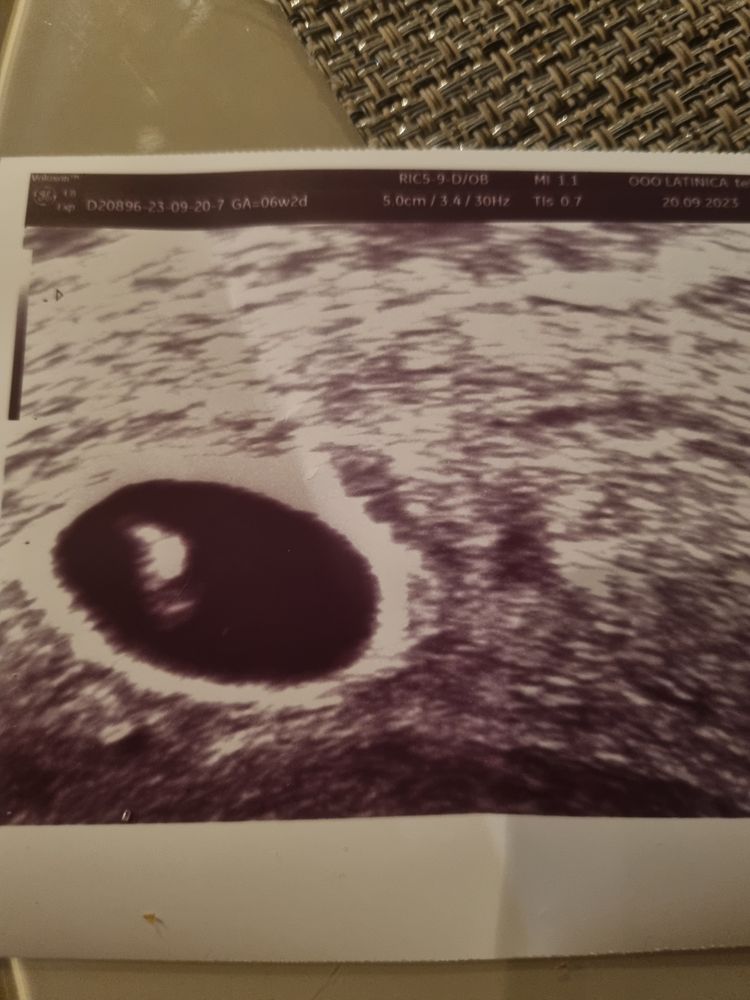

Екатерина, вот всяко разно мерила, только эмбрион видно Изображение

Диана, по мне так беленьким эмбрион (личиночка 😁) сереньким снизу желтое тело

Екатерина, не, снизу это тоже эмбрион, где светлое- там сердечко мелькало